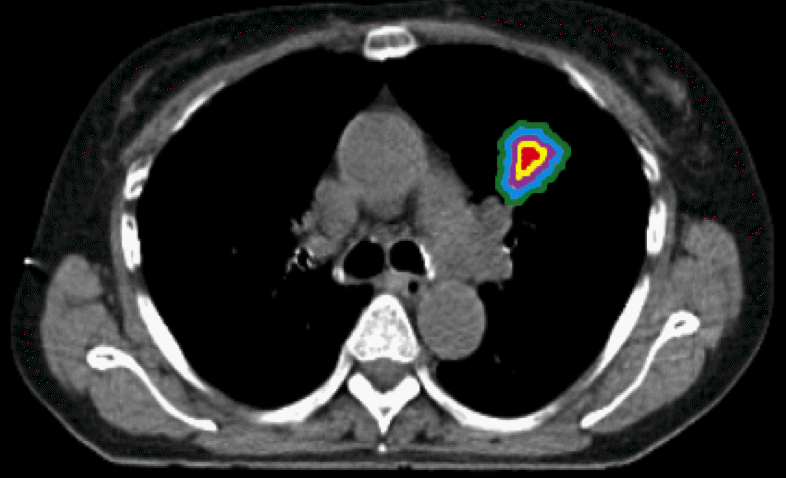

Improved treatment of tumors with novel image tools

In the treatment of cancer, which is one of the greatest threats to public health, new treatments are continually being developed.Our research aims at developing tools that are needed for planning of surgery and radiotherapy and for evaluating the effect of treatment regimes as early as possible. This includes new segmentation methods based on machine learning.